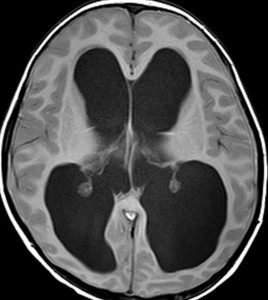

高度の水頭症です。でもこれは幼少期から10年くらい同じような水頭症で経過していると考えられる例です。右側の画像で中脳視蓋グリオーマがみえます。中脳水道狭窄の緩徐な進行によって生じた停止性水頭症 arrested hydrocephalusです。この時点で普通の大学生で無症状です。水頭症に対してはなにも治療をしないで経過を見ます。停止性水頭症にシャント手術は絶対にしてはいけないし,内視鏡による第3脳室開窓術も思わぬ合併症を招くことがあります。